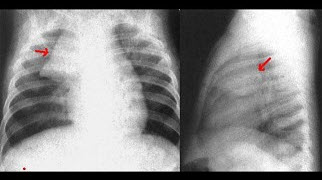

女,51岁,胸闷、咳嗽、咳痰2月余,3年前被确诊为子宫平滑肌肉瘤,结合胸片,最可能的诊断是()

A.粟粒型肺结核

B.肺转移瘤

C.结节病

D.胶原病

E.真菌病